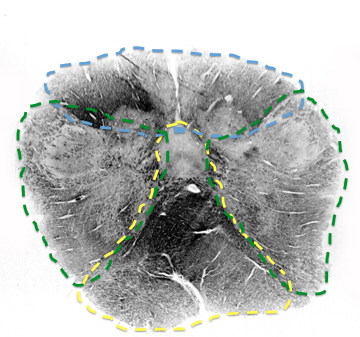

What supplies top of medulla until the fasciuli go away?

posterior spinal artery

includes gracile nulcueus, cuneate fasiculus and nucleus

What supplies olivary complex in the caudal to middle medulla?

vertebral

when does the posterior spinal disappear from the medulla?

by the time its only cuneate nucleus

when does the anterior spinal replaced? what replaces it to feed middle rostral medulla?

when CN 8 comes in

replaced by paramedian branches of basilar